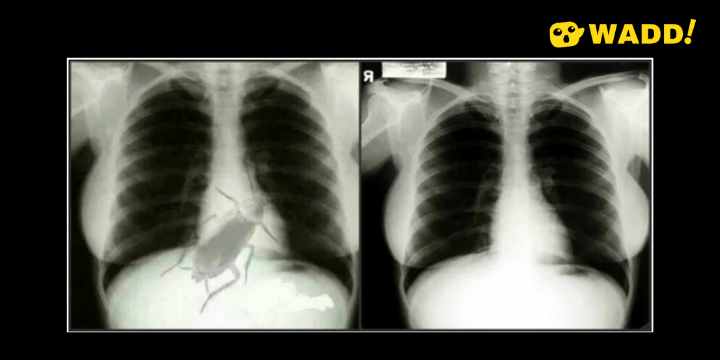

The Fact: The viral image is doctored. With a reverse image search of the chest X-ray, it was the famous Marilyn Monroe's X-ray.

Left - 'fake' cockroach viral image. Righ - Marilyn Monroe's X-ray image. Image source via snopes